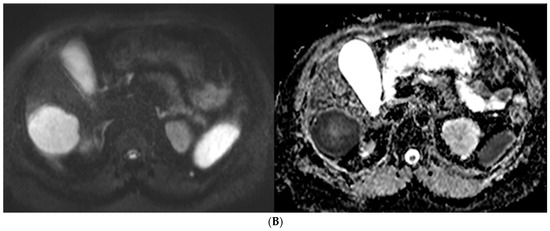

3. Results